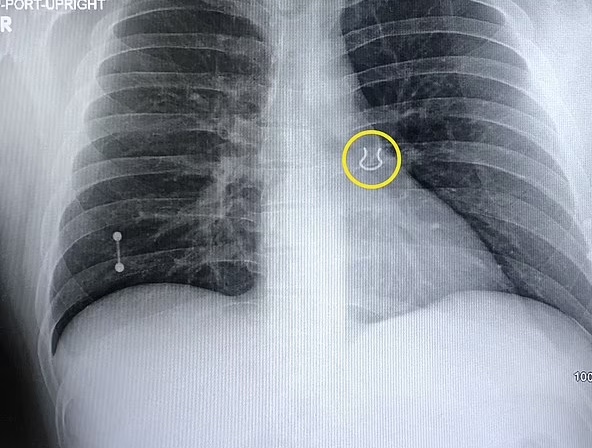

Ele precisou bater um raio-x e foi informado sobre o item. Os médicos suspeitam que a joia se moveu ligeiramente para dentro do pulmão nos últimos anos.